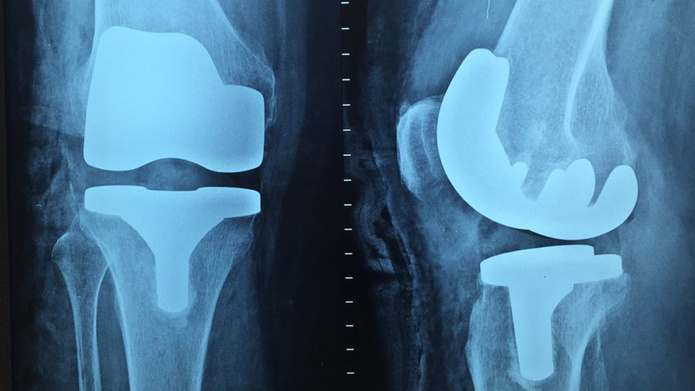

شانس موفقیت کاشت ایمپلنتهای پزشکی افزایش مییابد

به گزارش «نبض فناوری»، محققان دانشگاه پلیتکنیک SPbPU با همکاری پژوهشگرانی از دانشگاه ایالتی سن پترزبورگ، پوششهایی را برای ایمپلنتهای تیتانیوم ایجاد کردند که باعث رشد سریعتر بافت استخوانی میشود.

دکتر ماکسیموف از محققان این پروژه میگوید: «ما روشی برای استفاده از پوشش نازک (با ضخامت نانومتری) و یکنواخت اکسید تیتانیوم روی ساختارهای شبکهای تیتانیوم ایجاد کردهایم که میتوان از آن بهعنوان بهبود عملکرد ایمپلنتها استفاده کرد.»

محققان این پروژه خواص طیف وسیعی از پوششهای ایمپلنت تیتانیوم را آزمایش کردند که از نظر ترکیب، ضخامت و ساختار با هم متفاوت داشتند. این پوششها با استفاده از لایهنشانی اتمی (ALD) روی سطوح مورد نظر اعمال شدند. پس از اصلاح ایمپلنتها، نتایج موفقیتآمیزی از آزمایش این پوششها روی سلول در شرایط درونتنی و برونتنی بهدست آوردند.

دکتر نظروف از پارک تحقیقاتی، دانشگاه ایالتی سن پترزبورگ گفت: «در حال حاضر ما شروع به استفاده از نانوذرات نقره روی سطح تیتانیوم کردهایم؛ زیرا این عنصر شیمیایی خواص آنتیباکتریال جالب توجهی داشته و خطر رد ایمپلنت را کاهش میدهد.»

به گفته دانشمندان، بخش مهمی از مطالعه این است که اندازه و مورفولوژی نانوذرات درست انتخاب شود؛ بنابراین، نقره اثرات سمی بر سلولهای زنده ایجاد نمیکند و همزمان خواص مفید پوشش قبلی ایجاد شده نیز حفظ میشود.